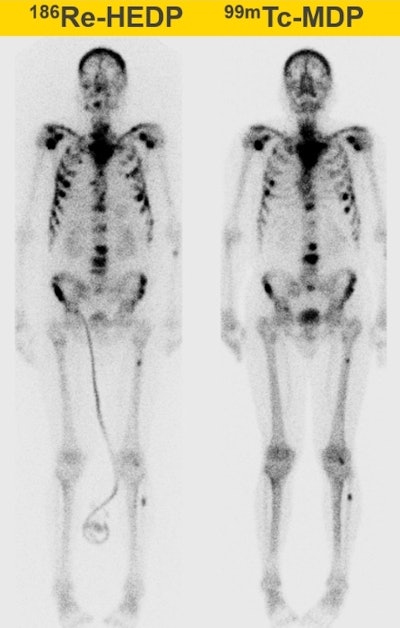

One study, for instance, examined Re-186 HEDP treatments of bone metastases from prostate cancer, where the dose-limiting factor is blood marrow toxicity. The researchers created a model to estimate the whole-body absorbed dose for an individual patient before radionuclide injection, using the level of administered activity and preinjection biochemical measurements. Results revealed the whole-body absorbed dose was correlated with blood toxicity. "This showed that we can predict the toxicity prior to treatment and thus adjust and personalize it," Denis-Bacelar explained.

She also described her recent work on image-based dosimetry of Re-186 HEDP treatments (European Journal of Nuclear Medicine and Molecular Imaging). The study calculated SPECT-based absorbed doses for 379 bone lesions in 22 patients treated with 5 Gbq. Results revealed a wide range of absorbed dose, both between lesions in one patient and between patients, even though all received the same activity.